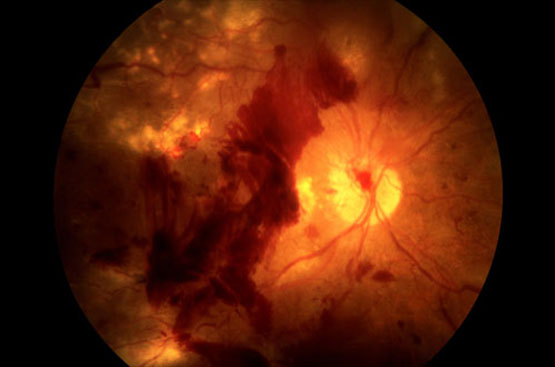

Retinografia

Imaging a colori e ad infrarossi per identificazione e monitoraggio di nevi coroideali e patologie corioretiniche

Fundus Oculi

Valutazione oftalmoscopica del polo posteriore e della periferia retinica